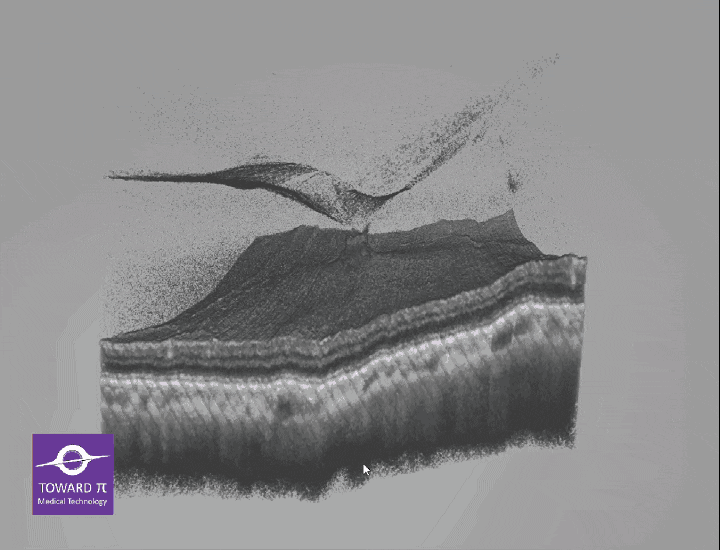

Obrazowanie 3D

Odtwarzanie struktury i naczyń w rekonstrukcji trójwymiarowej

Wykorzystuje zaawansowane algorytmy sztucznej inteligencji do automatycznej segmentacji warstw siatkówki i naczyniówki, pomiary ilościowe segmentu przedniego i tylnego, analizę jaskry oraz kwantyfikację przepływu krwi, a także rekonstrukcje 3D